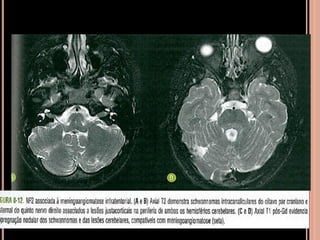

 Schwannomas volumosos se estendendo para a

cisterna pontocerebelar com intensa impregnação

pelo Gd; na sequência em T2 tem hipersinal

heterogêneo;

 Múltiplos nódulos, em T1 pós contraste importante

realce compatíveis com schwannomas;

SCWHANNOMAS

Pequenas lesões no CAI, bem mais caracterizada

nas aquisições volumétricas(3D CISS);

Aspecto de “sorvete de casquinha” quando lesões

maiores com extensão pontocerebelar;

Hipo em T1 e hiper heterogêneo em T2;

Impregnação pelo Gd homogênea se pequenos e

heterogênea se grandes;

RM

 Iso ou hipoatenuante em relação ao parênquima e realce pelo meio

de contraste, no ângulo pontocerebelar;

 Schwannomas vestibulares

 Schwannoma de nervo trigêmio